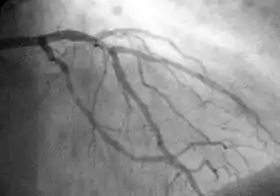

A coronary angiogram showing the left coronary circulation

Coronary catheterization uses pressure monitoring and blood sampling through a catheter inserted into the heart through blood vessels in the leg or wrist to determine the functioning of the heart, and, following injections of radiocontrast dye, uses X-ray fluoroscopy, typically at 30 frames per second, to visualize the position and volume of blood within the heart chambers and arteries. Coronary angiography is performed during a cardiac catheterization and used to determine the patency and configuration of the coronary artery lumens.